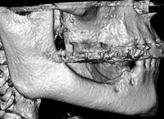

Indkærvninger i mandiblen kan ligeledes give udfordringer (8). Lingvalt i mandiblen findes konkaviteter i form af fossa

submandibularis i molarregionen og fossa sublingualis i præmolarregionen, som bl.a. indeholder blodkar og kirtelvæv (Fig. 2). Risiko for perforation til disse strukturer i forbindelse med udboring af implantatlejet er naturligvis større, når fossae er særligt udtalte. Omhyggelig palpation og evt. ”ridge mapping” (9), hvor morfologien vurderes på basis af mål af slimhindetykkelsen og en savemodel (1), samt røntgenundersøgelse er essentielt til vurdering af de anatomiske forhold.

Fig. 2. Fossa submandibularis (markeret med pile) ses oralt i den posteriore del af mandiblen på en 3-d-model i et softwareprogram til analyse af CBCTscanninger. Fig. 2. The submandibular fossa (marked with arrows) is located lingually in the posterior part of the mandible on a 3D model in a software program for analysis of CBCT scans. Fig. 3. A. Længdemål fra toppen af processus alveolaris til canalis mandibulae på et CBCT-snit i det sagittale plan (ca. 13 mm). B. Længdemål fra toppen